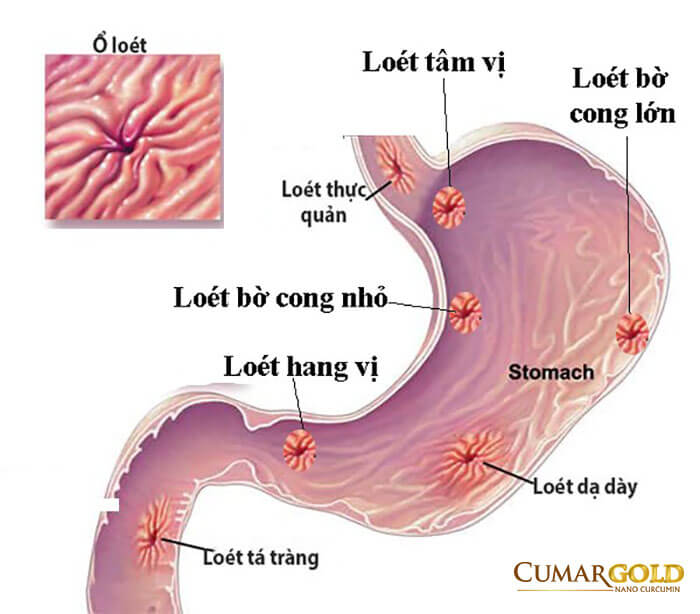

Hang vị là phần nằm ở gần cuối dạ dày còn bờ cong nhỏ dạ dày là phần mép phải của dạ dày, nằm ở vị trí kéo dài từ tâm vị cho đến hết lỗ môn vị. Viêm hang vị bờ cong nhỏ là sự tổn thương vùng niêm mạc ở hang vị ngay vùng mép phải của dạ dày tính từ góc bờ cong nhỏ tới lỗ môn vị. Tình trạng này kéo dài có thể gây ra các bệnh như xuất huyết dạ dày, ung thư dạ dày vô cùng nguy hiểm.

Viêm hang vị viêm bờ cong nhỏ có hai loại: viêm hang vị bờ cong nhỏ xung huyết và viêm hang vị bờ cong nhỏ dạng hạt. Cụ thể

Một trong các lý do bị loét hang vị bờ cong nhỏ hay xảy ra tình trạng loét vì khi bụng đói, dạ dày rỗng, vùng niêm mạc và dưới niêm mạc sẽ tự động co lại tạo thành các nếp gấp khúc. Bờ cong nhỏ của dạ dày là vị trí có nhiều nếp gấp nhất trong dạ dày. Cũng bởi vậy, đây là nơi trú ẩn lý tưởng có các vi khuẩn có hại, giúp chúng dễ dàng ẩn náu và lan rộng dần ra. Vì trú ngụ ở sâu trong cùng của nếp gấp, các vi khuẩn này khó bị tiêu diệt bởi các loại thuốc và cũng không chịu nhiều tác động từ môi trường acid trong dạ dày.

Các tổn thương phát sinh giữa các nếp gấp trong bờ cong nhỏ của dạ dày cũng khó được phát hiện hơn so với các vùng khác trong dạ dày. Do đó, các tổn thương thường không được điều trị khi mới phát sinh mà chỉ khi viêm loét nặng, chúng ta mới phát hiện được và điều trị.

- Loét hang vị bờ cong nhỏ là biến chứng thường gặp nhất của bệnh nhân viêm hang vị, bờ cong nhỏ. Sự tác động của các acid kéo dài khiến lớp nhầy bảo vệ niêm mạc dần mất đi tác dụng tạo ra các ổ loét nghiệp trọng hơn. Các ổ loét khiến cho việc tiêu hóa thức ăn ngày càng kém, gây ra những cơn đau âm ỉ kéo dài, đặc biệt là khả năng bị ung thư hóa dạ dày tăng cao.